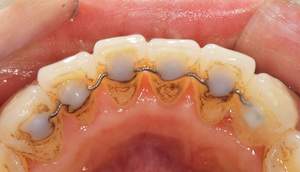

歯石除去

治療前

治療後

| 年齢 | 36歳・男性 |

| 主訴 | 歯石をとりたい |

| 治療内容 | 歯石除去 |

| 治療期間 | 30分 |

| 費用 | 約2,000円 |

| リスク・副作用 | ・歯ぐきの炎症が強いと歯石を取る際に出血することがあります。 ・処置後に歯がしみることがあります。 ・歯と歯の間に隙間ができるので、息が漏れ発音しにくいと感じることがあります。 ・歯ぐきの炎症が軽減すると歯ぐきが引き締まり、歯が長く見えることがあります。 |